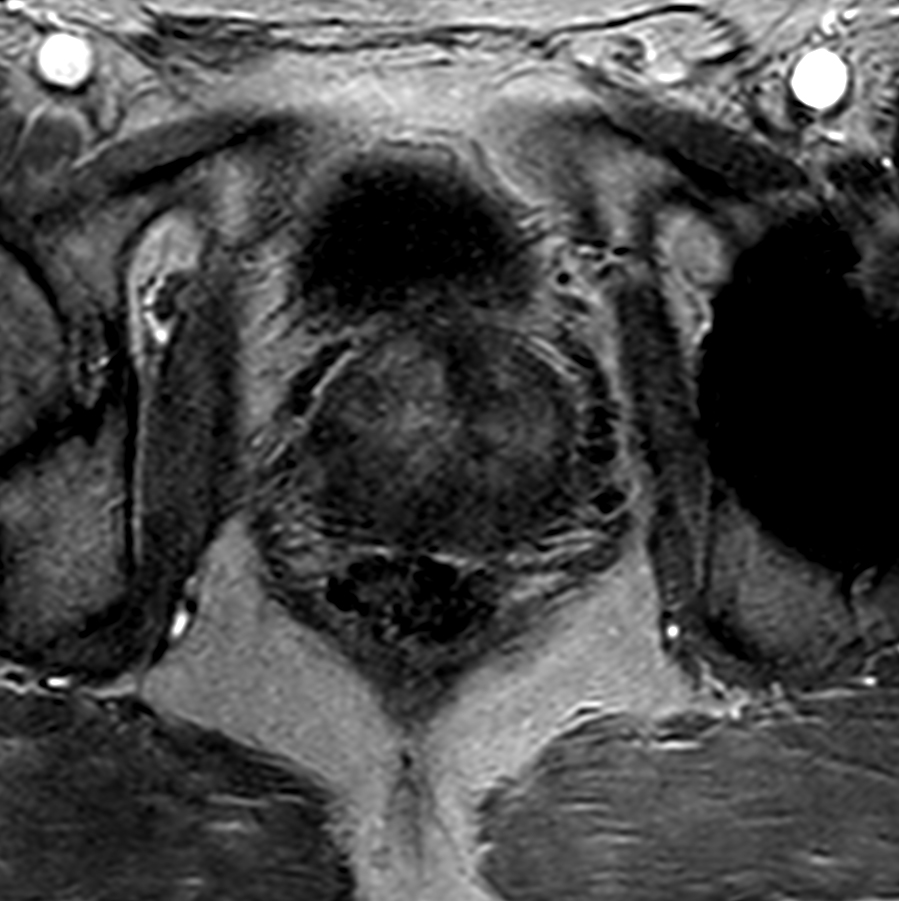

Axial T2w TSE